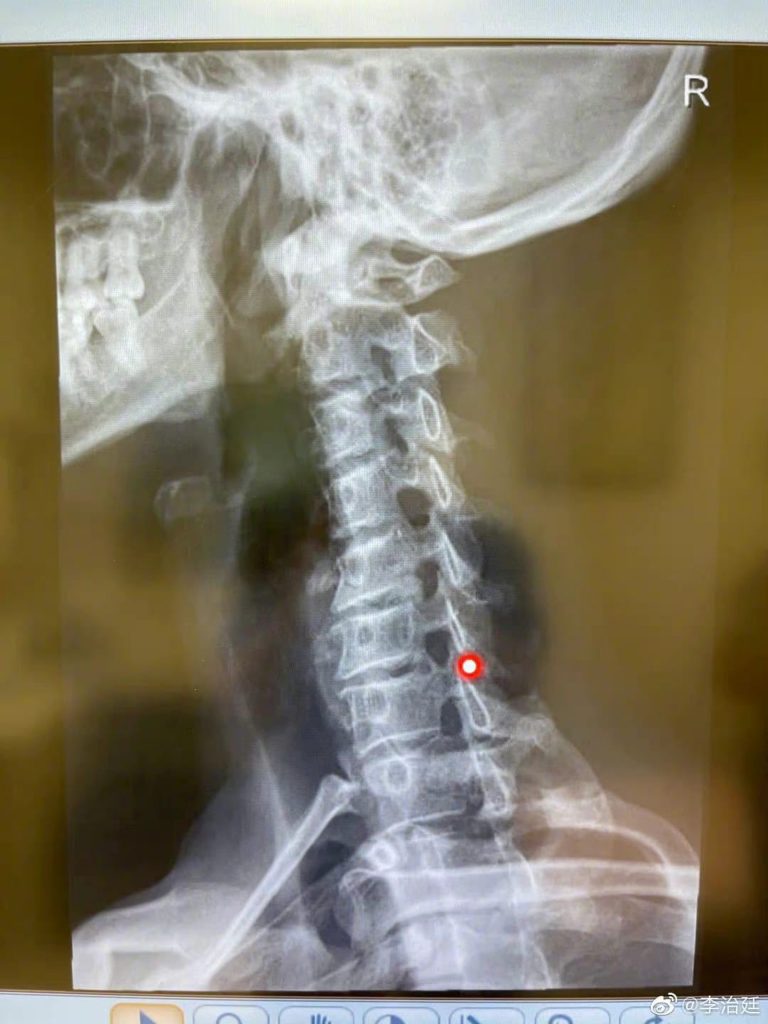

他呼吁大家要保护颈椎,注意身体健康,还在社交网上晒出颈椎X图,留言:“来……给大家演奏一首《我的颈椎》,34岁的李治廷60岁的颈椎。”非常懂得自娱。

一身肌肉的李治廷,向来都有做健身的习惯,在节目中讲到体能的活动,绝对难不到他,但节目组为他进行身体检查时,却发生了一段小插曲,原来现年34岁的李治廷,颈椎已退化到60岁,明显是长期劳损,李治廷解释他读书时经常低头温习,入行后又要弹吉他创作音乐,又要低头读剧本,长期成为低头族,令他的颈椎劳损,希望在节目中情况能得到改善。